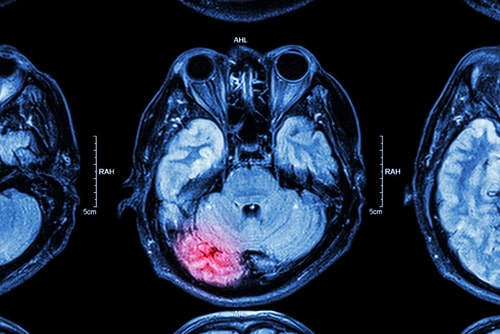

- Intracranial hemorrhage – These can occur after the brain experiences trauma, resulting in bleeding within the brain and inside the skull. This form of injury is an emergency and must be addressed immediately. If not promptly addressed, comas or death can occur.